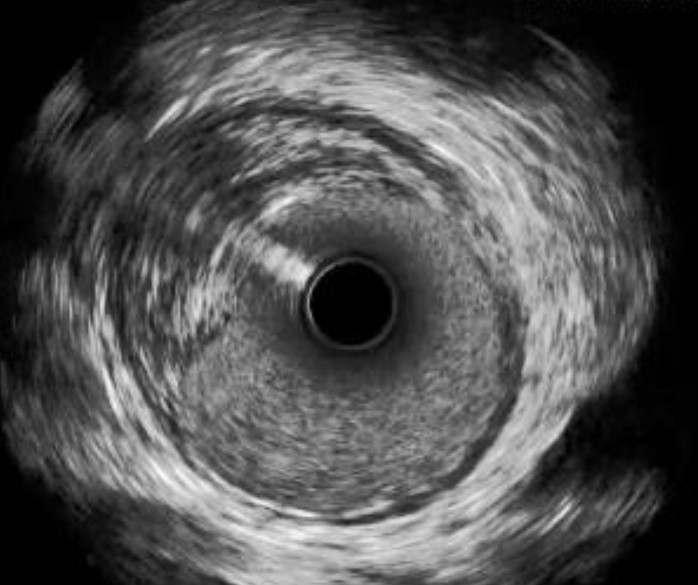

Catéter para toma de imágenes coronarias Opticross de 40 MHz vs. Catéter para toma de imágenes coronarias Opticross de 60 MHz

El Catéter para toma de imágenes coronarias Opticross de 60 MHz proporciona una mayor visibilidad del stent con una resolución más clara para confirmar la aposición adecuada del stent a la pared del vaso.

OPTICROSS 40 MHz

OPTICROSS HD Imaging Catheter 40MHz

Axial resolution: 38 µm